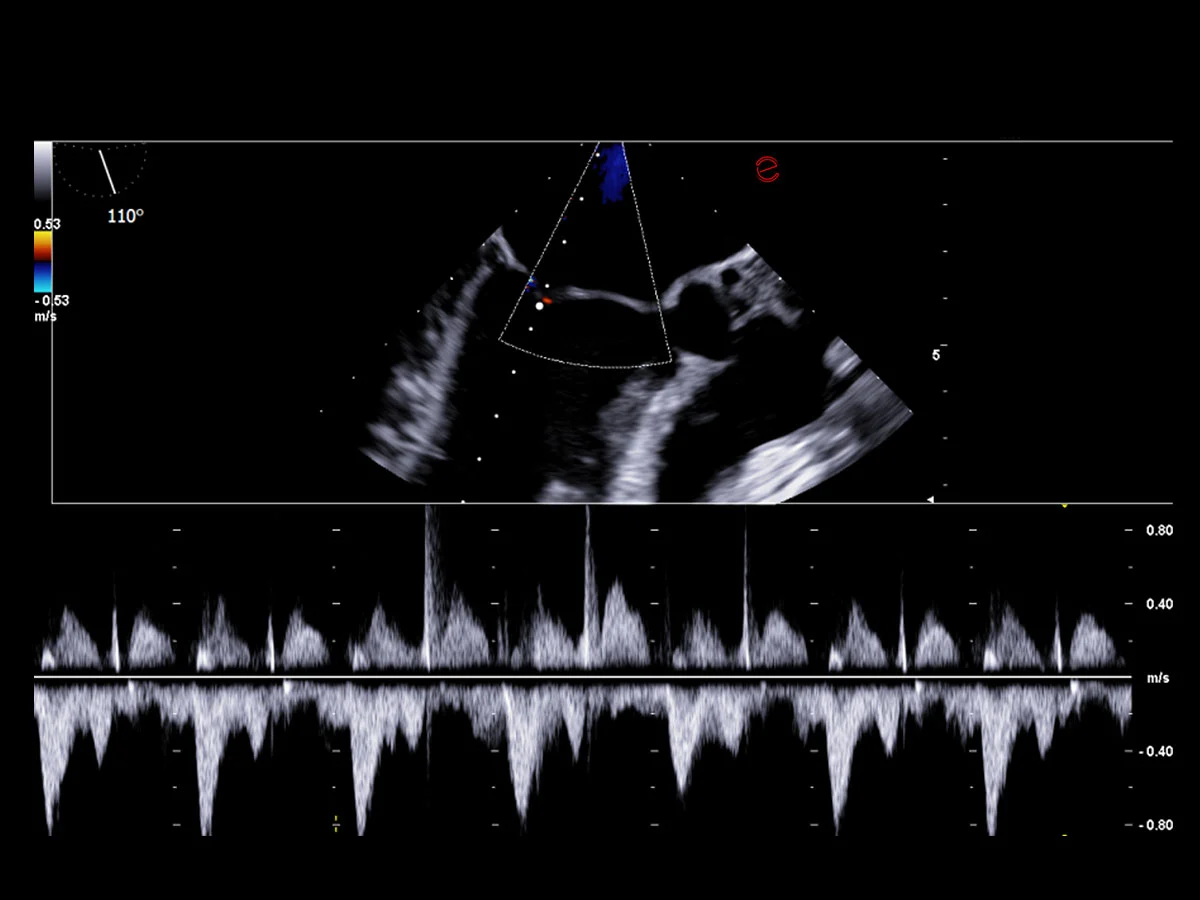

High-performance transesophageal echocardiography probe quality

Esaote’s TEE probe is designed to ensure exceptional image quality and diagnostic versatility, offering detailed visualization of posterior cardiac structures when transthoracic access is limited. It enables precise assessment of the left atrium, appendage, cardiac valves, and thoracic aorta, providing vital information in complex scenarios, such as endocarditis, suspected thrombus, or intraoperative monitoring. Its ergonomic design ensures patient comfort and optimal control during probe manipulation, and its seamless integration with Esaote systems supports real-time guidance for structural interventions and critical diagnostics.